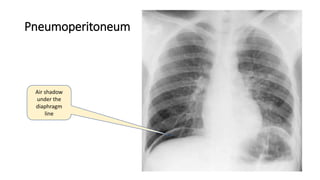

Pneumoperitoneum

Air shadow

under the

diaphragm

line